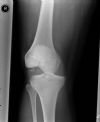

Dislocated Right Knee - AP (1)